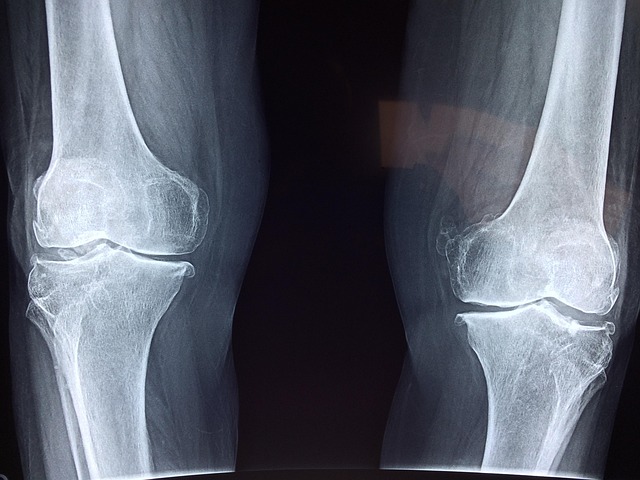

- 퇴행성 관절염: 연골이 닳아 관절 간 마찰이 증가하면서 통증 유발. 50대 이후 여성에게 흔하다.

무릎통증 치료방법, 단계별 접근이 필요

통증의 원인과 정도에 따라 치료는 다양하게 구성된다.

- 수술치료: 연골 손상이 심각하거나 보존 치료 효과가 없을 경우 관절경 수술 또는 인공관절 수술 시행